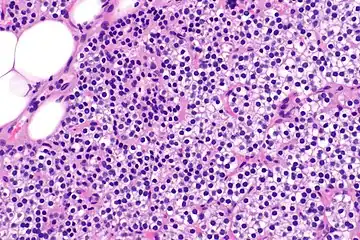

Parathyroid hyperplasia high mag.

Primary hyperplasia of the parathyroid gland, results from both hypocalcaemia and increased phosphate levels by decreasing expression of calcium sensing receptors and vitamin D receptors at the parathyroid gland.[8][4] These decreases in receptor expression lead to hyperfunctioning of the parathyroid. Hyperfunction of the parathyroid gland is thought to exacerbate primary hyperplasia which evolves further to a secondary more aggressive hyperplasia. Histologically, these hyperplasic glands can be either diffuse or nodular.[24] Primary hyperplasia, usually resulting in diffuse polyclonal growth is manly related to reversible secondary hyperparathyroidism. Secondary hyperplasia of the parathyroid gland is more often a nodular, monoclonal growth that sustains secondary hyperparathyroidism and is the catalyst in the progression to tertiary hyperparathyroidism. Nodular hyperplastic glands in tertiary hyperparathyroidism are distinctly larger in both absolute size and weight up to 20-40-fold increases have been reported.[25][26][24]

Parathyroid glands are normally composed of chief cells, adipocytes and scattered oxyphil cells.[27][14] Chief cells are thought to be responsible for the production, storage and secretion of parathyroid hormone. These cells appear light and dark with a prominent Golgi body and endoplasmic reticulum. In electron micrographs, secretory vesicles can be seen in and around the Golgi and at the cell membrane. These cells also contain prominent cytoplasmic adipose.[27][14] Upon onset of hyperplasia these cells are described as having a nodular pattern with enlargement of protein synthesis machinery such as the endoplasmic reticulum and Golgi. Increased secretory vesicles are seen and decreased intercellular fat is characteristic.[27][24] Oxyphil cells also appear hyperplasic however, these cells are much less prominent.